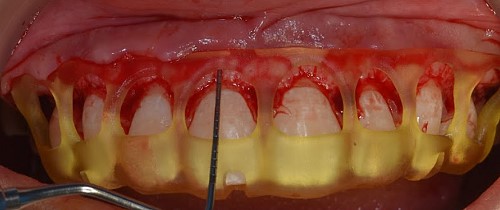

The STL files of the maxilla and teeth were manipulated using BlueSky Plan software (see Fig. 8). Subsequently, a guide was designed to facilitate osseous resection, adapting to both the teeth and the maxilla (see Fig. 9). In the surgical phase, a full-thickness flap was raised in the upper jaw, and the guide was affixed (see Figs 10 and 11). The guide snugly conformed to the bone, and its position was verified with a margin distance from CEJ set at 3 mm (see Figs 12 and 13). Postoperative results at 2 and 12 months are shown in Figs 14 and 15. The final outcomes closely resembled the Digital Smile Design (DSD) simulation conducted before treatment (see Fig. 16).